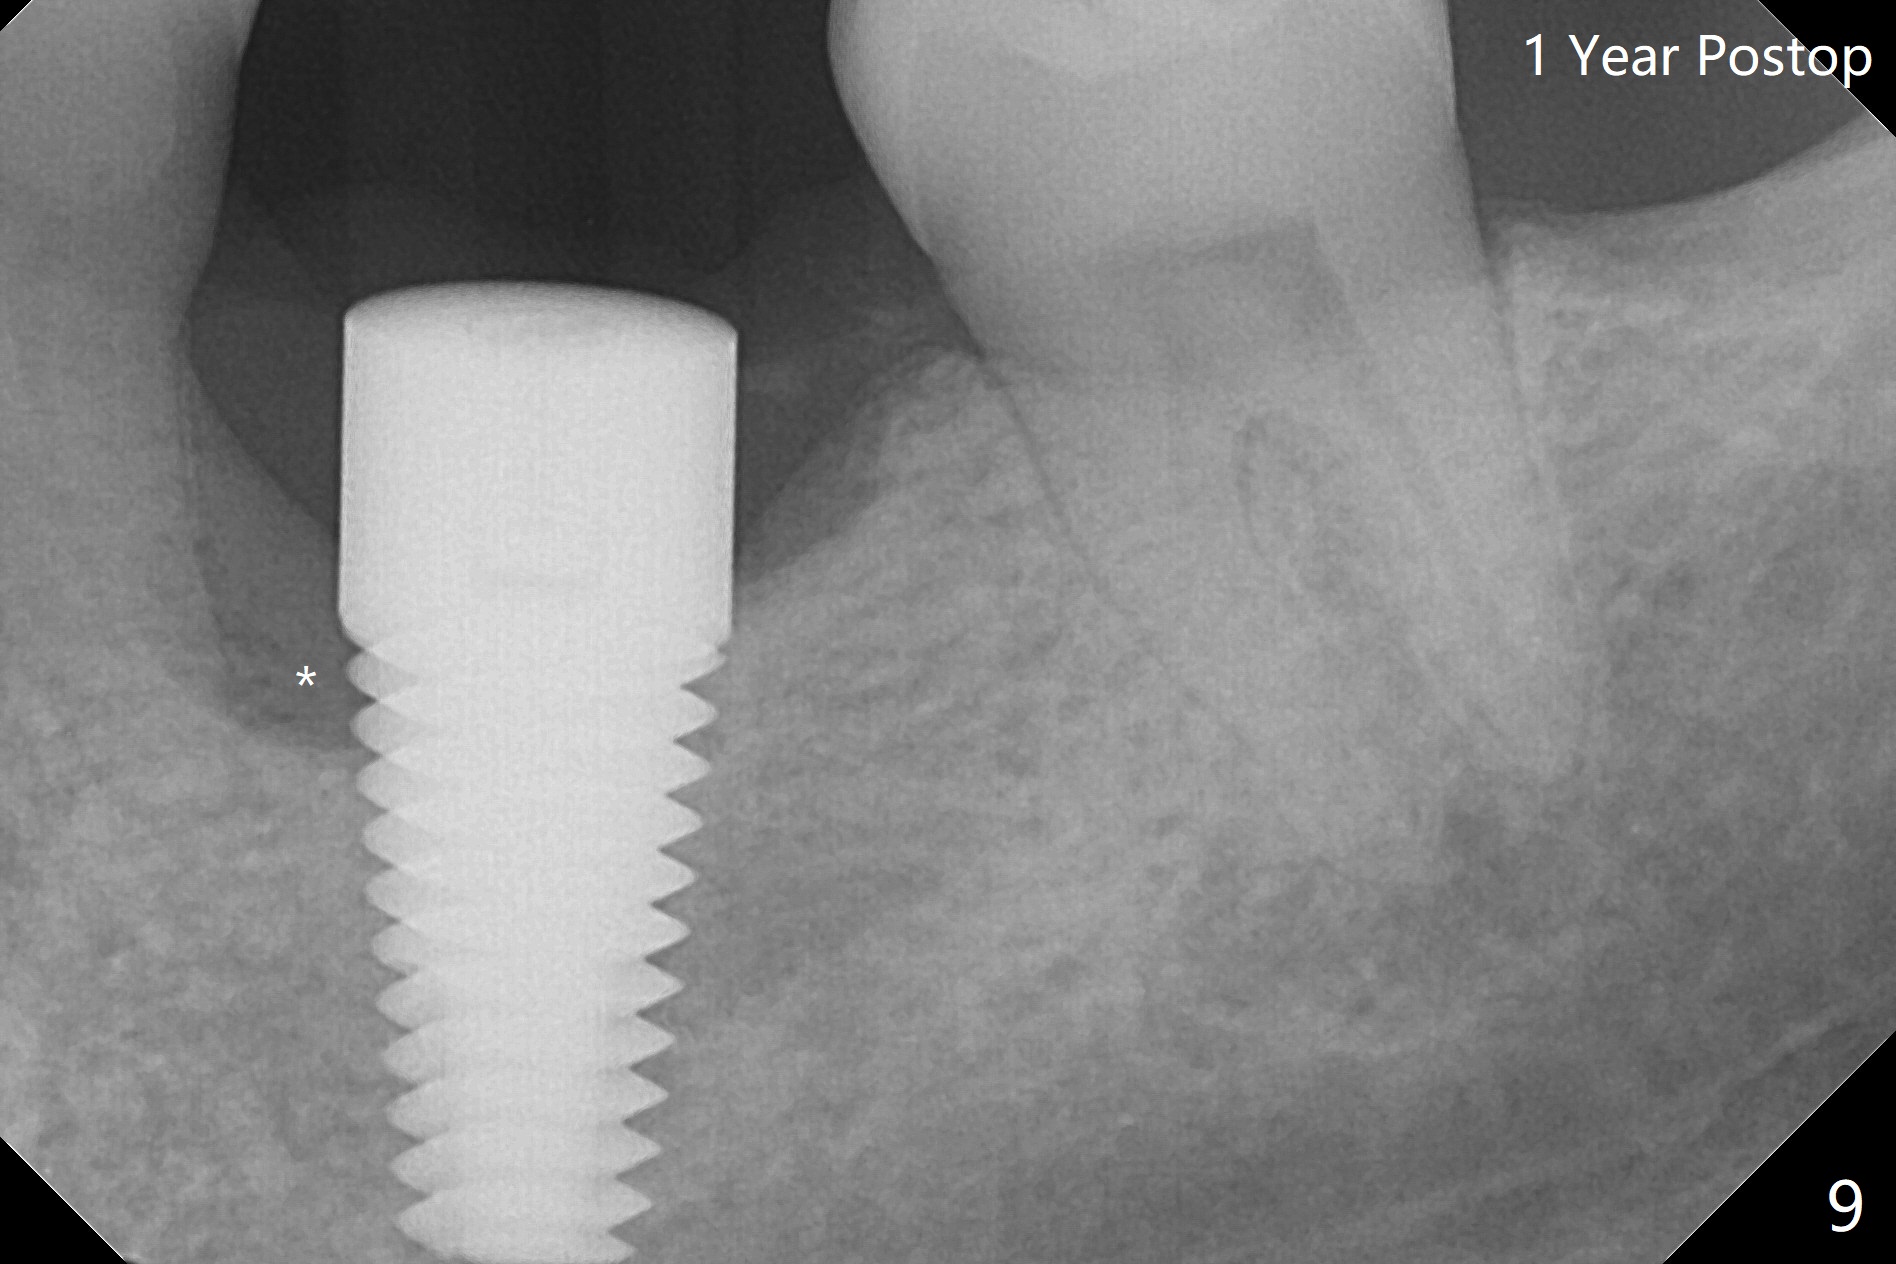

After 4.0x10 mm drill with 9 mm offset for 4.5x10 mm bone-level implant at #19, a 4.5x17 mm tissue level tap is inserted with apparently low torque (probably without reaching the depth). When a 4.5x14 mm tissue level implant is placed with high torque, a 4.5x7.3 mm drill is used for ~ 6.5 mm. The implant loses the primary stability with over-insertion (Fig.1). When an abutment is placed, the implant is critically loose. Mixture of autogenous bone, Osteogen and allograft is placed in the osteotomy. The implant regains stability with better placement level for restoration (Fig.2). In fact the bone density around the implant increases (Fig.2 *). For the first 7 days postop, the patient has to take Advil. When he returns for follow up 8 days postop (Fig.3), the pain decreases, while there is minor degree of lower lip paresthesia. Medrol Dose Pak and Tylenol III are prescribed. The implant is loose 24 days postop; after removal of the implant and apparently infected bone graft, a 7x14 mm dummy implant is inserted with <20 Ncm and 3-4 mm clearance (Fig.4). A longer dummy implant seems to improve stability (Fig.5). So does the definitive implant (Fig.6,7, 25 Ncm), but it is placed low. The gingiva looks healthy 13 days postop (2nd placement). A healing cap will be placed for restoration ~ 3 months postop. CT will be taken if the implant needs to be backed up to determine whether there is enough bone buccolingually. Due to coronavirus and prolonged placement of a healing abutment with poor oral hygiene, the buccal gingiva of the implant is erythematous 1 year postop (Fig.8 healing cap just removed) with bone loss (Fig.9,10 *). Sticky bone seems to be necessary. A 6x5 mm abutment with slots will be placed to hold periodontal dressing in place.